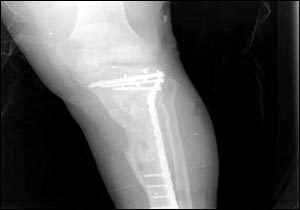

烏代傷腿的X光照片

7月24日,美國國防部通過由美國資助的伊拉克電視臺、兩家阿拉伯衛(wèi)星電視臺以及美國本土的CNN(有線新聞網(wǎng)絡(luò))將薩達姆的兩個兒子烏代和庫賽遭美軍擊斃慘死的照片公諸于世,同時被曝光的還有1996年烏代遇刺后所拍的傷腿的X光片。據(jù)悉,近60的伊拉克人收看這檔節(jié)目。此前,美軍中央司令部的里卡多·桑切斯中將在巴格達舉行新聞發(fā)布會時說,判斷烏代和庫賽被打死的依據(jù)是在現(xiàn)場發(fā)現(xiàn)的牙齒以及曾任薩達姆助手的目擊證人的指認。